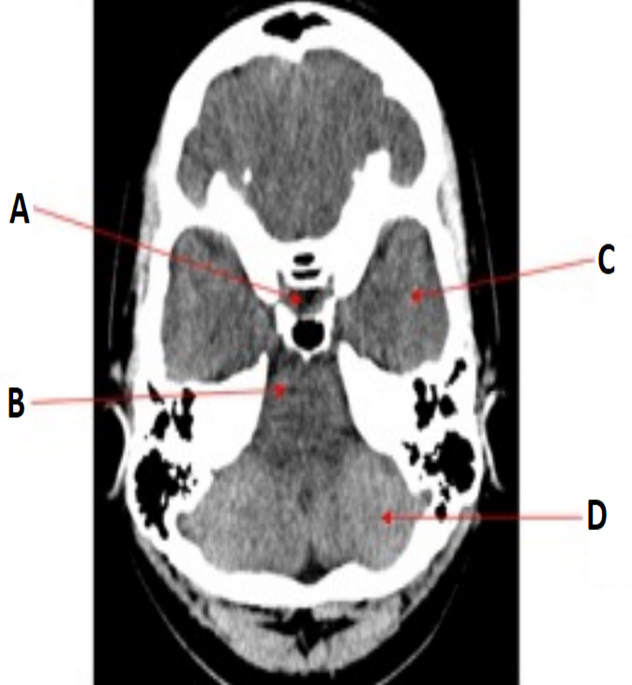

label

•A = Pituitary fossa

•B = Pons

•C = Temporal lobe

•D = Occipital lobe